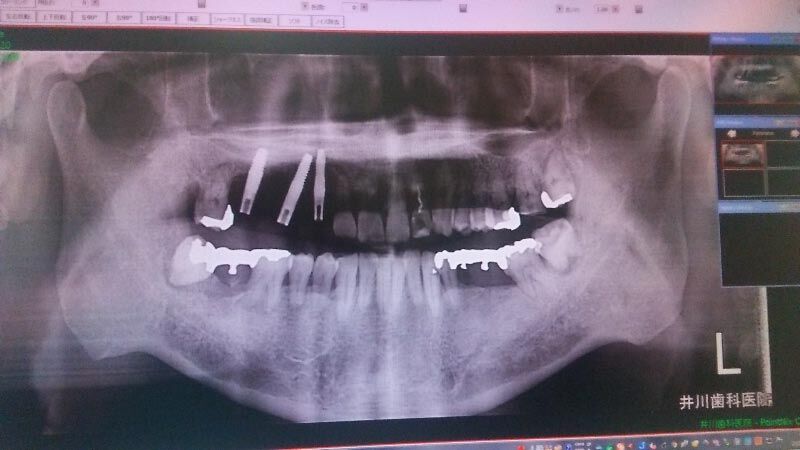

そして、ジャジャジャーン、CTスキャンで私の顎を中心に、頭骸骨のレントゲンを撮る↓。

先生は、これを観て、歯石をとった後の最終処置として、根が浮いている3番とすでに抜けた4番の隣の5番を抜いて、3本の人工歯根を立て、その歯根に4本の歯を装着するといという計画を提案しました。人工歯根の位置は、下の写真の緑色の位置です。

上記の抜歯に続いて、同日に、インプラントの手術をしました、下の写真は術後に撮ったレントゲンです。左の方に写っているマッチ棒のような細い3本が人工歯根です。直径は4mmです。